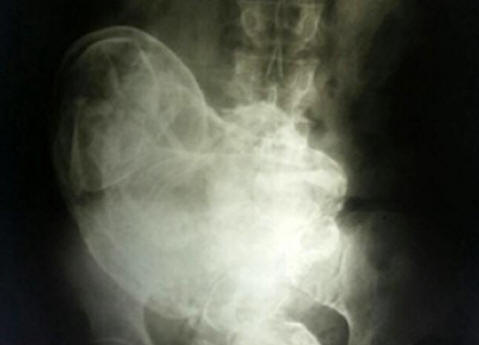

V lůně 84leté brazilské ženy objevily zkamenělý plod 44 let. To se stalo, když kvůli nesnesitelné bolest břicha žena konzultovala s lékařem, který ji vyrobil Rentgen Na obrázku viděli zkamenělé embryo. Tento jev obdržel v lékařském použití jméno litografie. Lithopedion – zkamenělý plod dělohy, který zemřel v děloze nebo v břiše dutina, která poté podstoupila kalcifikaci. Je to vzácné jev, který se vyskytuje hlavně v případě, že plod během léčby zemře mimoděložní těhotenství. Protože není přirozený způsob, jak se zbavit takového plodu, to tělo odhalí kalcifikace, aby se zabránilo poškození tkání plodu tělo nosiče. Lékaři, kteří ji vyšetřili, dospěli k závěru že plod zemřel v 28. týdnu těhotenství. Nicméně z chirurgie pacient to odmítl odstranit. Marocký případ Tento jev je velmi vzácný, takže k jeho výskytu obvykle dochází zaznamenané historiky. Tento je popsán v roce 2012. Rezident malá vesnice ležící v blízkosti Casablanky, Maroko, matka tří dětí Zahra Abutalib naposledy otěhotněla ve věku 26 let. Devět měsíců těhotenství plod prošel bez komplikací. V nemocnici se však stala svědkem smrt spolubydlící v nemocnici, mladá matka, která zemřel na operačním stole v důsledku císařského řezu. Ne podařilo zachránit své dítě. Bojí se, že takový osud může Očekávejte, že od ní bude dojemná Zahra, sbírající věci nemocnice, rozhodování porodit doma. Během několika příštích dny strašně trpěla porodními bolestmi, ale dlouho očekávanými dítě nikdy nepřišlo na svět. Brzy se úplně zastavil pohni se v lůně a žena se rozhodla, že dítě „usne“. Zahra dobře si pamatoval místní mýtus o „spícím dítěti“. Údajně, pokud ne porodí ho, pak bude po celý život bránit čest své matky. Proto ne zvláště se obával o její stav, zejména od kontrakcí již se neopakuje. To trvalo čtyřicet šest let, dokud nedávno, již ve věku 75 let, se bolest náhle nevrátila. Zahra obrátil se k lékařům. Ultrazvukové vyšetření v městské nemocnici Rabat ukázal přítomnost cizí ženy v břiše těla, jejichž původ lékaři nedokázali vysvětlit. Byl provedl důkladnější vyšetření těla, podle výsledků které odborníci dospěli k závěru, že pevná hmota v těle Zahra není nic jiného než zkamenělé ovoce, které je ženským tělem zázračně mylně považován za orgán, a proto po dlouhou dobu ne vnímán jako cizí těleso. Operace trvala čtyři hodiny. Nakonec tým lékařů vedl Dr. Taibi Kuazzani podařilo se mu z ženského těla vytáhnout plod vážící o něco více než dva kilogramů a o délce 42 centimetrů. Takže téměř po půl století se Zahraino dítě konečně narodilo.

Fotografie z otevřených zdrojů Lithopedion je tvořen v těle ženy v případ fetální smrti, obvykle po mimoděložním těhotenství, i když existují případy jeho vzniku v děloze. Tělo matky vnímá mrtvé dítě jako cizí tělo, a v důsledku ochranné reakce je plod mumifikován. První podrobný popis takového případu sahá až do roku 1582, kdy je jisté Objevil se francouzský lékař při pitvě 68leté ženy zkamenělé ovoce, které zůstalo v lůně matky po dobu 40 let. Celoživotní těhotenství Podle lékařských statistik „kamenné děti“ mohou zůstat uvnitř člověka tak dlouho, dokud na dlouhou dobu. A 46 let není v žádném případě limit. Takže v lednu 2009 v roce 2007 z nemocnice v čínském městě Huangiaotang se stala 92letá místní obyvatel Huang Yuijun, který si stěžoval na velmi silnou bolest žaludek. Jaké bylo překvapení lékařů, když to zjistili starší žena … těhotná! Navíc těhotná po dlouhou dobu – 60 let! Její úžasný příběh podle Slunce začal zpět v roce 1948. Potom lékaři Huangovi řekli, že plod dříve zemřel narození v jejím lůně. K jeho odstranění byla nutná operace lékaři požadovali částku v místní měně odpovídající 150 dolarů. Když Huang slyšel ceny, jednoduše se otočil a odešel. „Tohle je v té době bylo hodně peněz, říká žena, víc než všichni členové mé rodiny vydělali za pár let. Proto i Neudělal jsem nic, rozhodl jsem se ignorovat lékařskou diagnózu. “ „Ignorování“ pokračovalo několik desetiletí, dokud nezanikl v lůně, dítě si znovu nepřipomínalo. “Nemohl jsem tomu uvěřit.” na vlastní oči, když zjistil, že v lůně je Yuijun dítě, “říká Dr. Liu An Bin z nemocnice Gwingsheng. – pro moje 40 let praxe jako lékař není nic víc Neviděl jsem nic zvláštního nebo překvapujícího. “ Porodnická a gynekologická nemocnice Xu Xiang Ming dodává: „Obvykle uvnitř se rozpadne mrtvý plod. Ale v tomto případě se jednáme vzácná událost. Stále není jasné, jak paní Yuijunová celou tu dobu zůstala v dobrém zdravotním stavu. “Další otázky způsobuje nejdelší pro dnešek v historii medicíny těhotenství 93leté Lisabonky s bydlištěm Maria Romandes, která v roce 1996 odešel do nemocnice a stěžoval si na silnou bolest žaludek. Jaké bylo překvapení lékařů, když to zjistili starší žena je těhotná se dvěma mumifikovanými plody 72 let! Babička si vzpomíná, že v roce 1924 onemocněla nemocná, přibírala na váze. Současně bylo pozorováno zastavení menstruační cyklus. Žena si uvědomila, že má nějaký problém na ženské straně, ale protože jsem se necítil zvlášť silné bolesti, Ani jsem k lékaři nešel. Po chvíli nevolnost pominula a Maria si stěžovala na své zdraví až na jaře 1996 let. Poté, co zjistili příčinu „choroby“, lékaři okamžitě podstoupil operaci a odstranil dvě dobře zachované znecitlivěné dvojčata. Odborníci se domnívají, že zemřeli na selhání výživa. Důvodem je nedostatek výživy tělo Marie Romandesové je nevyhodilo včas.